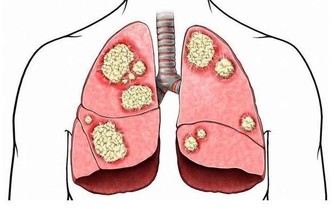

腸胃病科首席醫療顧問表示,大腸癌是我國第二癌症殺手,而華人則是患上大腸癌的最大群體。

大腸癌的早期有四大症狀

腫瘤阻塞,當腫瘤長至相當體積,或浸潤腸壁肌層時,

可引起腸管狹窄,腸腔變小,腸內容通過受阻。